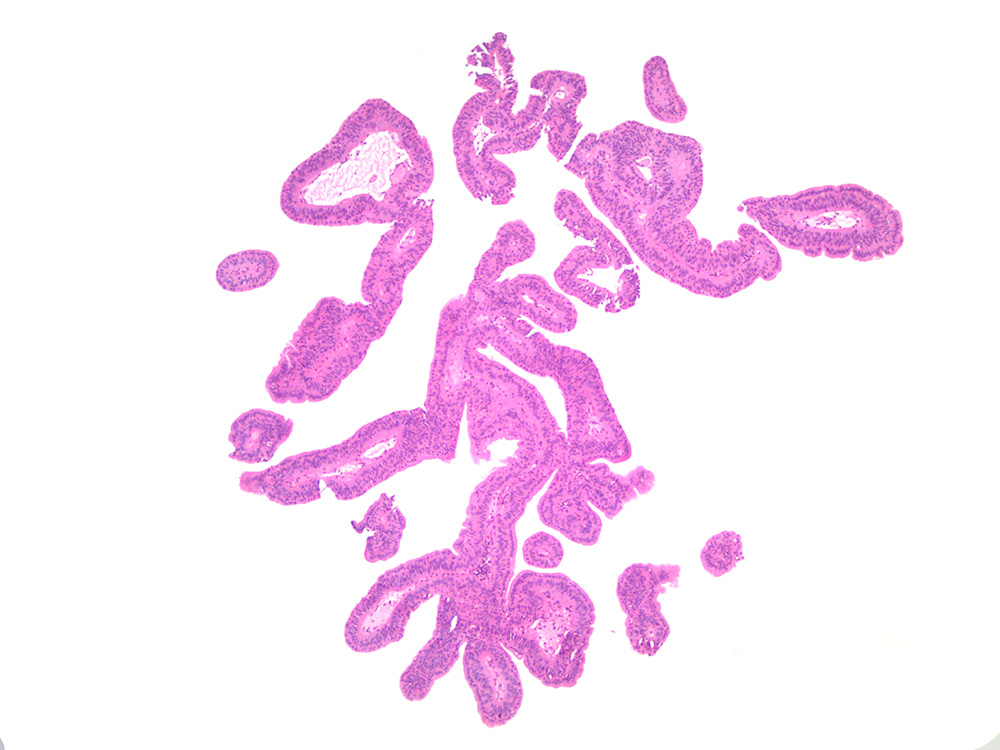

Consensus grade: Papilloma

Small papillary lesion in urinary bladder